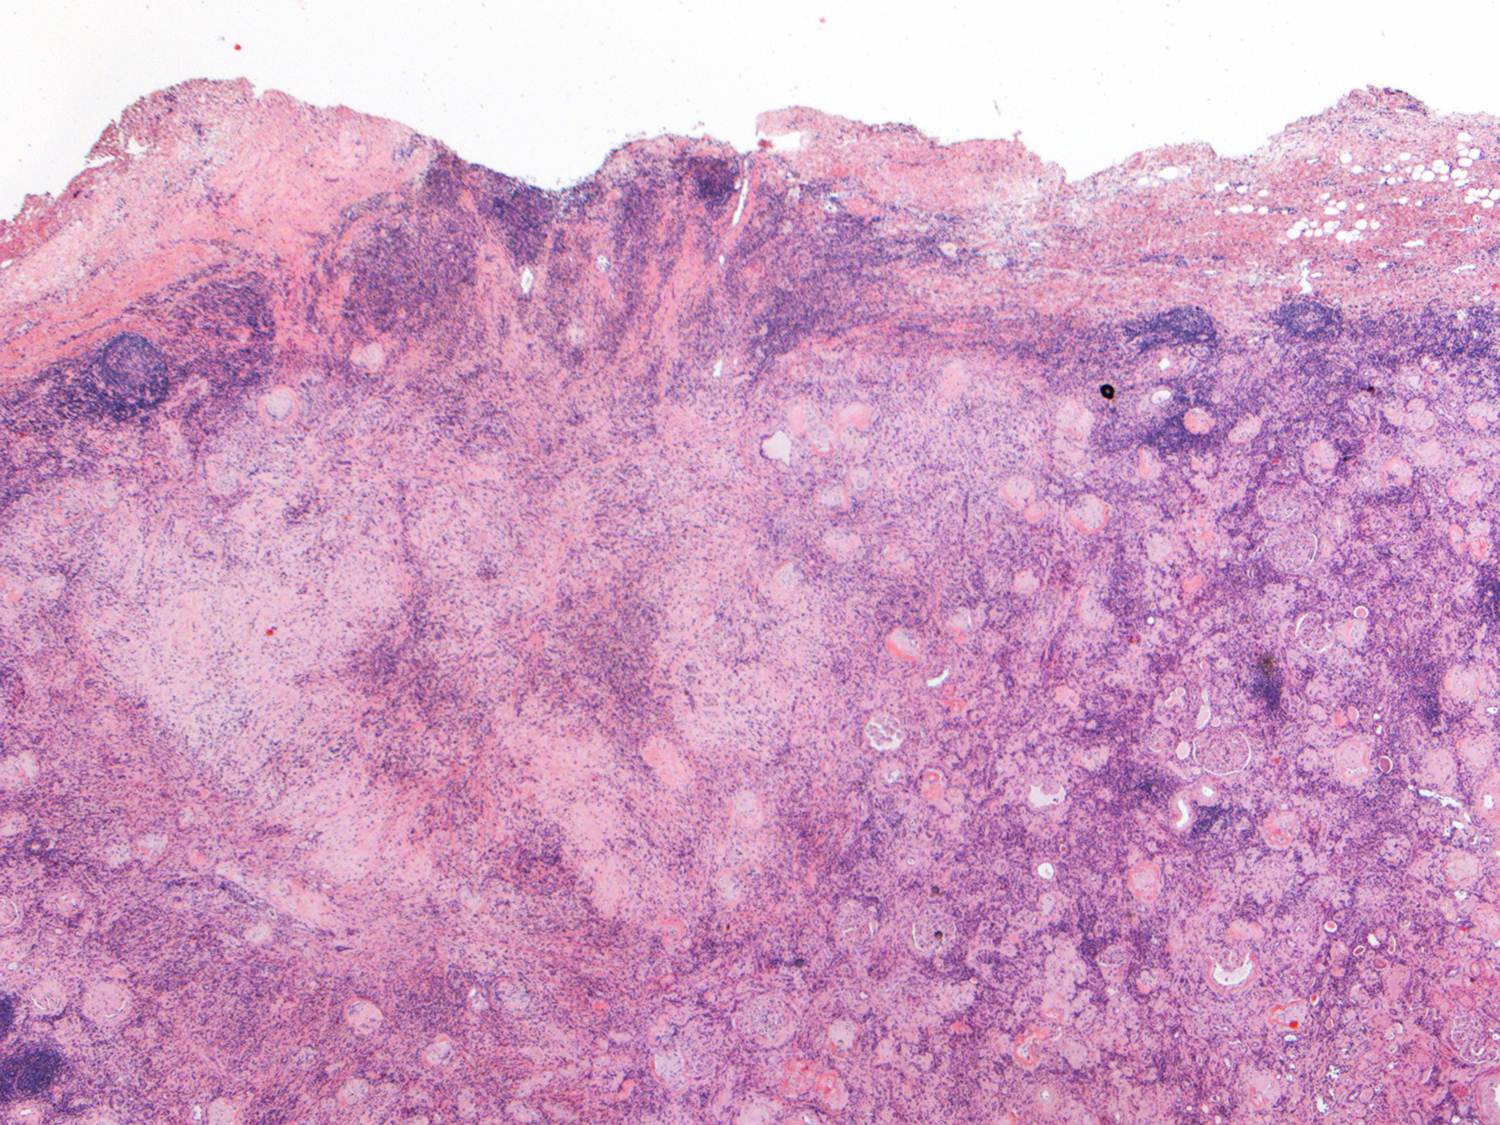

This is a low-power view of the renal cortex. There is diffuse global glomerulosclerosis involving approximately 80% of glomeruli. There is also significant tubular atrophy and interstitial fibrosis with associated areas of inflammation.

There was focal perirenal and intrarenal scarring with disruption of the renal capsule.